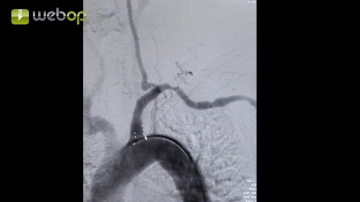

Angiographie

Toneinstellungen Darstellung der supraortalen Äste, insbesondere der Arteria subclavia sinistra. Markierung des Abgangs der Arteria subclavia aus dem Aortenbogen sowie deren Stenosierung.